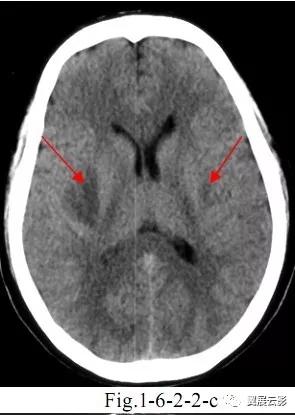

病例3:多发腔隙性脑梗死

腔隙性脑梗死为深部脑组织的小面积梗死,好发部位为基底节,丘脑,脑干,小脑及脑室旁白质区。应写清病灶的部位,大小,数目,鉴别诊断时应注意与脑血管周围腔隙相鉴别。